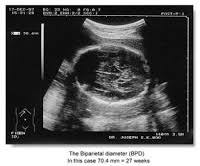

Gebelikte Hamilelikte Ultrason Ile Yapilan Olcumler

Gebelikte Hamilelikte Ultrason Ile Yapilan Olcumler from 1.bp.blogspot.com